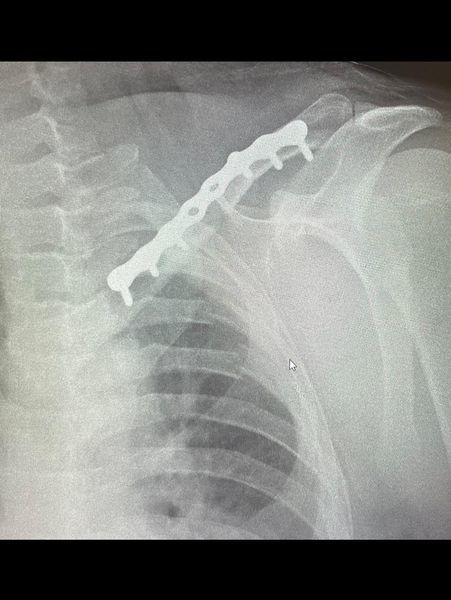

Воїн отримав тяжку травму під час виконання бойового завдання. Як наслідок - перелом 8 ребер, гідроторакс, перелом ключиці.

В реанімаційній залі прийняли, хірурги дренували легеню. В реанімації стабілізували, та прийшов час до синтезу ключиці.

Виконали металоостеосинтез за сучасною малоінвазивною методикою МІПО. 2 розрізи по 2 сантиметри. Під постійним рентген контролем - закрита репозиція та фіксація пластиною. Час операції 40 хвилин. Крововтрата 50 мл. Анестезія регіонарна.